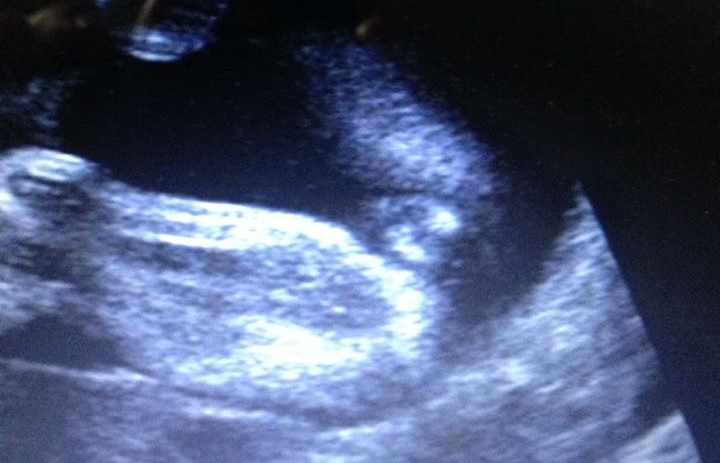

Hi, I've been told it's a boy and a girl... which is it? haha

These scans were taken at 24 weeksAttachment 28867Attachment 28868Attachment 28869

God I hope you're right haha! Depending on the angle it looked girl and other angles it looked boy.... At my 16w they said boy, 19w they said girl "she saw 3 lines" and now these pix at 24weeks lol (I might add - the tech didn't take these pix, I did with the dvd she gave me of the area..).

That's my other reasoning too Butterflies buttercups - that it could be swollen girl bits... argh lol! Again, even with the 3d scan I did, some angles showed girl and other angles it showed boy..

I also guess girl, at this stage you would see the penis for sure!! How strange the tech could not see / show you the gender at this point. But iI think if it were a boy you would definitely see a penis

I was 24 weeks in these photos.

Could it be a small penis or a huge clitoris..? lol

I'm thinking labia